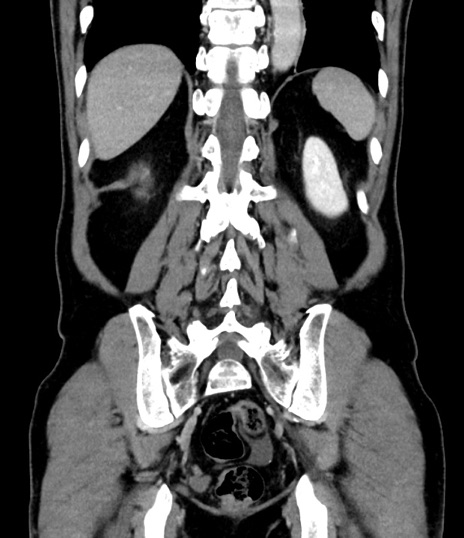

症例8(冠状断像)

【症例】 60歳代男性

【主訴】 黒色吐物

【現病歴】 4日前から嘔気自覚、2日前の朝食後にも嘔気あり、自分で手で嘔吐反射起こし嘔吐したところ血が混ざっていたため受診。

【既往歴】 5年前汎発性腹膜炎を伴う急性虫垂炎で手術、高血圧、前立腺肥大症、高脂血症

【身体所見】 腹部正中に手術癩痕あり 腹部平坦・軟圧痛なし膨満感あり

【データ】WBC 8400、CRP 4.54